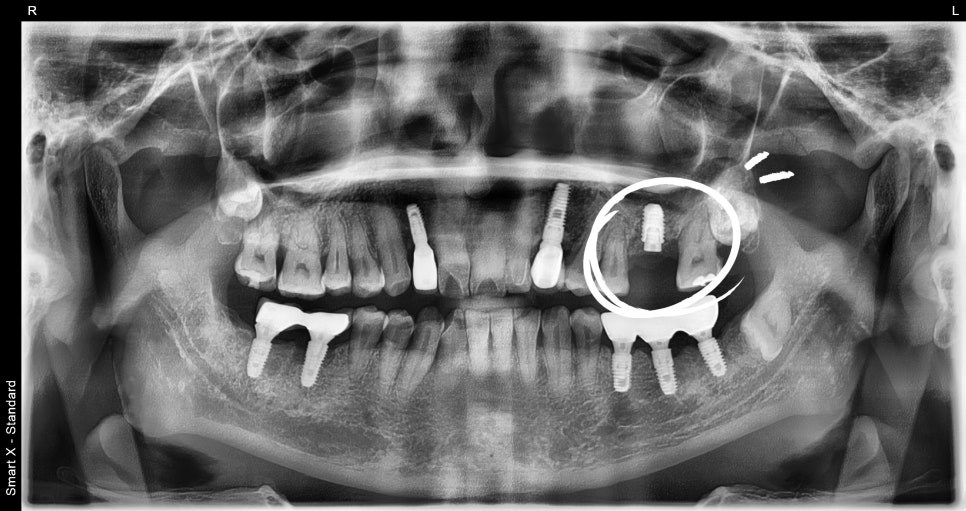

어금니 발치와 임플란트 식립

염증이 심한 어금니는 발치가 필요하였으며,

발치와 동시에 임플란트 식립이 진행되었습니다.

특히 어금니 부위는 뼈가 부족한 경우가

많기 때문에 뼈이식과 상악동 거상술이

함께 시행되었습니다.

임플란트치과에서는 이러한 고난도 수술을 통해

임플란트의 안정성을 확보합니다.

회복 기간과 2차 수술

임플란트 식립 후에는 뼈와 임플란트가 결합되는 시간이

필요합니다. 일반적으로 약 3개월 정도의 회복 기간을

거치게 되며, 이후 2차 수술을 통해 임플란트를

잇몸 위로 연결합니다.